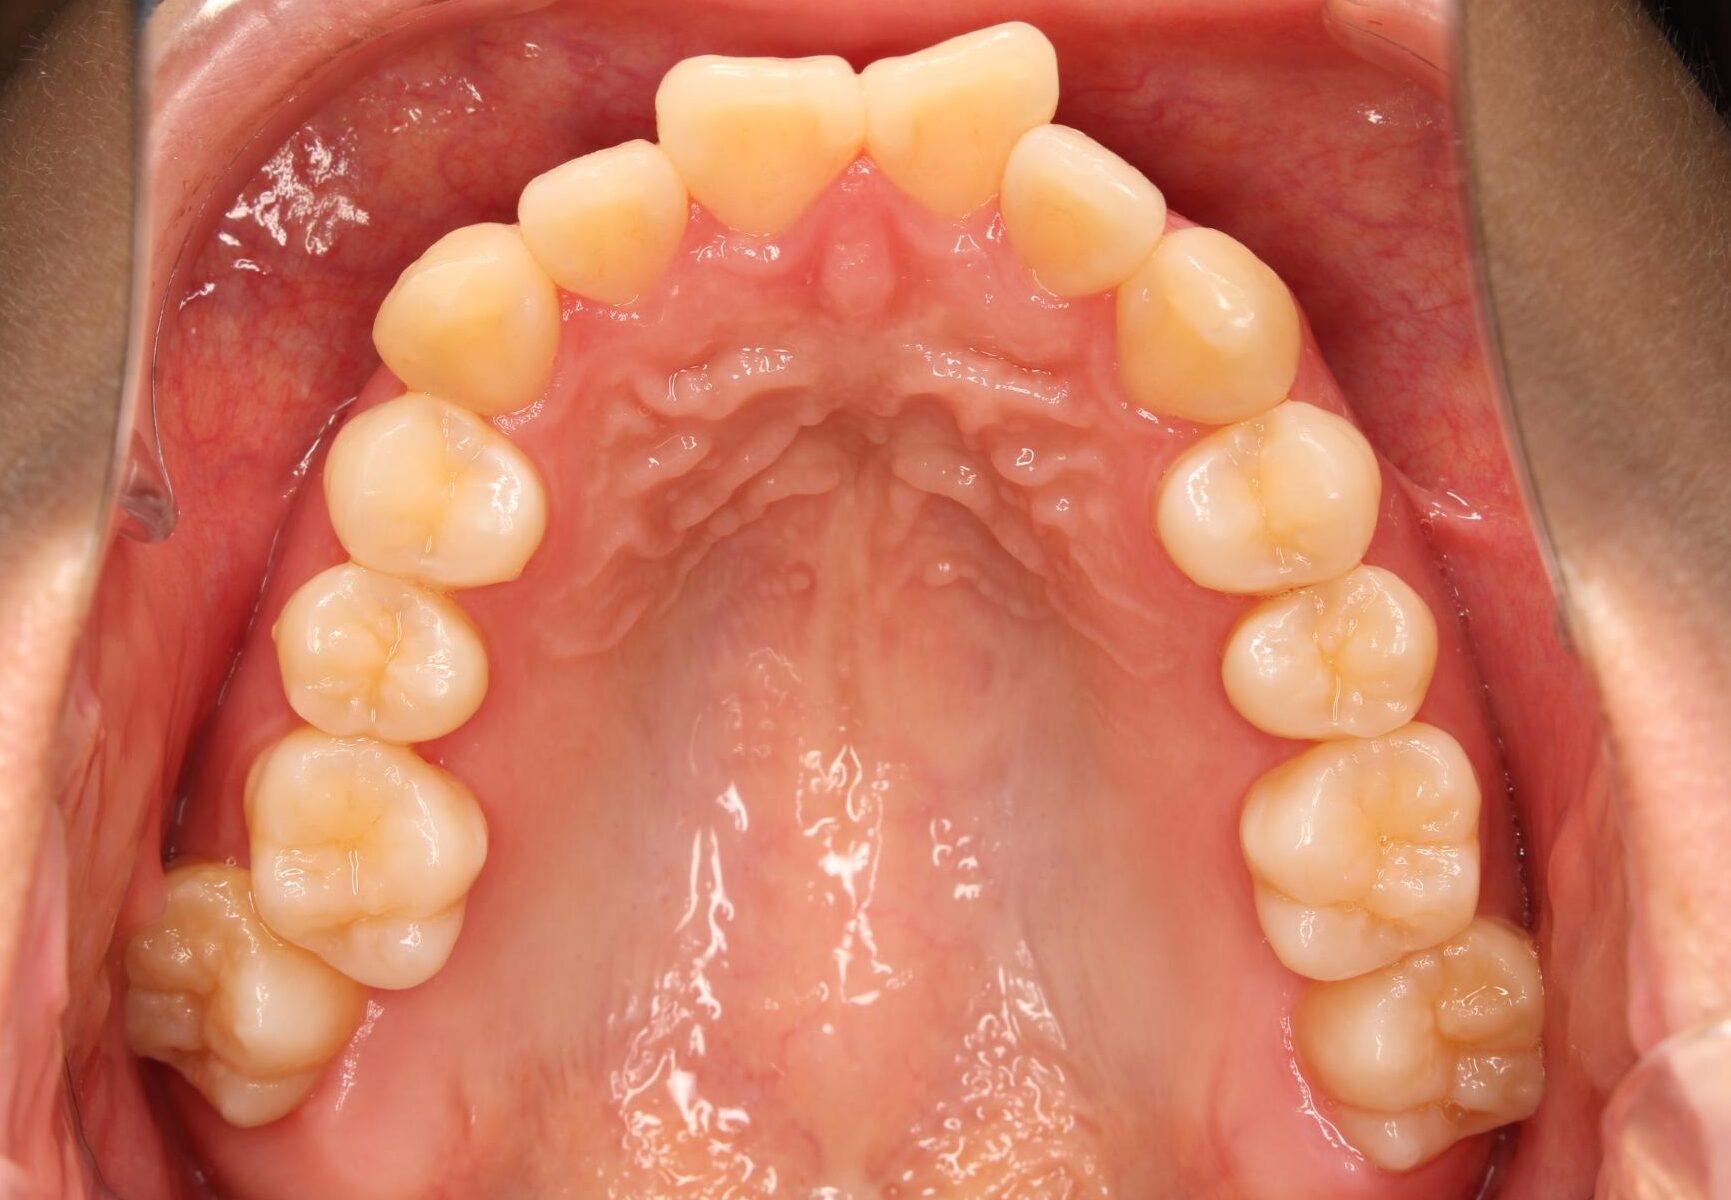

口腔内の変化

|  |  |

| ↓ | ↓ | ↓ |

|  |  |

口腔内の変化

|  |  |

| ↓ | ↓ | ↓ |

|  |  |

| 治療前 | でこぼこしている歯による歯磨きのやりにくさや、奥歯がしっかり咬んでいない鋏状咬合(すれ違い咬合)。 出っ歯による口の閉じにくさ(口唇閉鎖不全)と、正面から見た時のオトガイ部にできる梅干し様のシワやイーラインから飛び出た口元(口ゴボ)。 機能面も審美面も気にしていた患者さんです。 治療中もなるべく装置を目立たせたくないため、ハーフリンガルでの治療となりました。 |

| 治療後 | 上下の歯がお互いにはまり込み、全体的に緊密な咬み合わせになっています。 出っ歯が治り、口元の突出感が改善されて綺麗なEラインを獲得しました。 すれ違い咬合や叢生(歯のでこぼこ)も治って歯磨きがしやすく、嚙みやすい状態になっています。 |